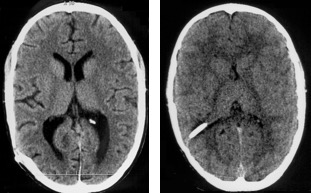

l’imagerie de référence

du fait du drainage, le patient valvé a le plus souvent des ventricules de

taille inférieure à la normale, de plus, son encéphale est rigide (très peu compliant) ; lors d’une obstruction de valve, les ventricules se dilateront donc peu pour une pression qui peut être très élevée.

inversement, les ventricules peuvent rester larges sans être sous pression.

pour éviter les retards d’intervention ou les interventions intempestives, il est donc indispensable de disposer d’une imagerie de référence (scanner ou IRM).

celle ci doit être faite :

- chez un patient asymptomatique

- après l’âge de 5 à 6 ans (taille ventriculaire stabilisée)

- au moins six mois après une révision de valve (retour des ventricules à la normale)

- et validée par l’absence de complication de valve dans les mois qui suivent

l’imagerie de référence doit être identifiée, archivée et disponible à tout moment pour l’équipe de neurochirurgie de garde qui sera amenée à prendre le patient en charge, ce qui nécessite une logistique assez légère et surtout de l’organisation pour être systématique.